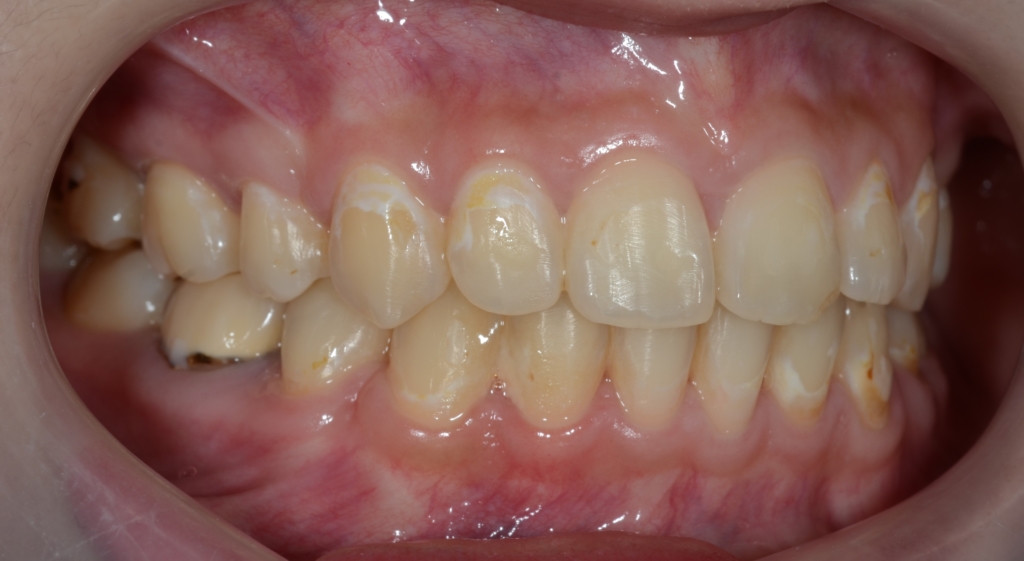

【After】

【保定】 上下ともフィックスタイプ&クリアリテーナー

【治療期間】 2年10か月間

矯正治療の結果、狙い通りに口元をスッキリさせることが出来て、横顔もEラインに収めることが出来ました。

ついでに、歯並びの比較です

上段が矯正治療前、下段が矯正治療後